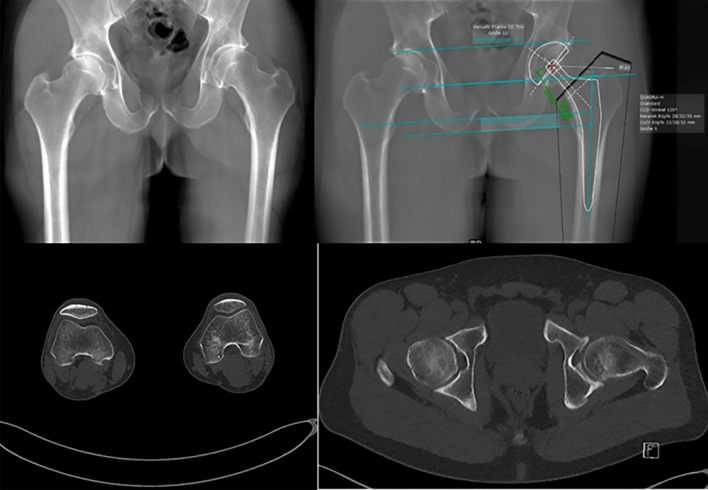

The two key findings of this study are that (1) the scaling deviation can lead to a planning error regarding the trochanter tip distance of ≥ 3 mm in 25% and ≥ 6 mm in 2% of the patients, (2) the newly developed tin-filtered ultra-low-dose CT scan protocol enables reconstruction of high-quality radiograph-like images which can readily be used for THA templating (Fig. 4, top left) with remarkably low radiation dose.

Fig. 4.

Top left: Radiograph-like image reconstructed from CT image data. Top right: THA templating performed on radiograph-like image. Bottom left: Rotation of femoral condyle. Bottom right: Rotation of femoral neck

Templating on a 2-D radiograph-like image of the pelvis reconstructed from CT image data eliminates this potential magnification error (Fig. 4, top left and right). Other advantages include (a) direct visualization of the femoral offset and torsion and (Fig. 4, bottom) (b) use of familiar and efficient 2-D planning method and (c) verification of correct patient positioning during the CT scan regarding all aspects. In select complex cases, the scan can be extended to include all of the pelvis as well as the ankle and allow 3-D planning with a minimally greater radiation dose (0.74 mSv vs. 0.58 mSv).